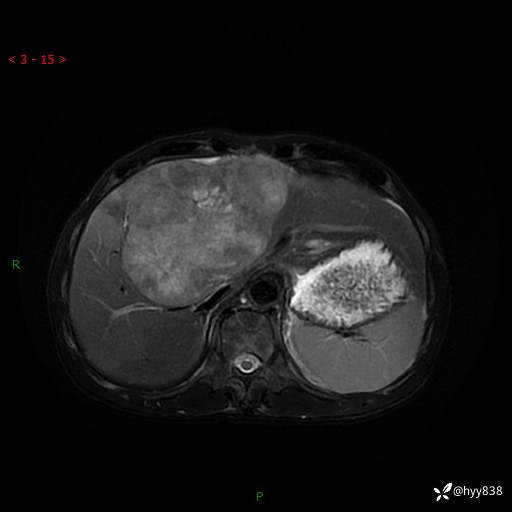

【患者信息】:58岁/男

【主诉】:发现肝占位2天

【现病史及既往史】:患者2天前于当地市第五医院查上腹部磁共振提示:肝脏S4段占位性病变,肝ca可能,胆囊结石,腹膜后多发肿大淋巴结,无剑突下及右上腹疼痛不适,无明显反酸、嗳气,无畏寒、头晕、头痛,无尿频、尿急、尿痛等不适,今为求进一步治疗特来我院就诊,门诊以“肝占位”收住我科。 患者病程中精神、睡眠、饮食尚可,大小便正常、体力体重无明显变化

【检查】:肝脏MRI】平扫+增强